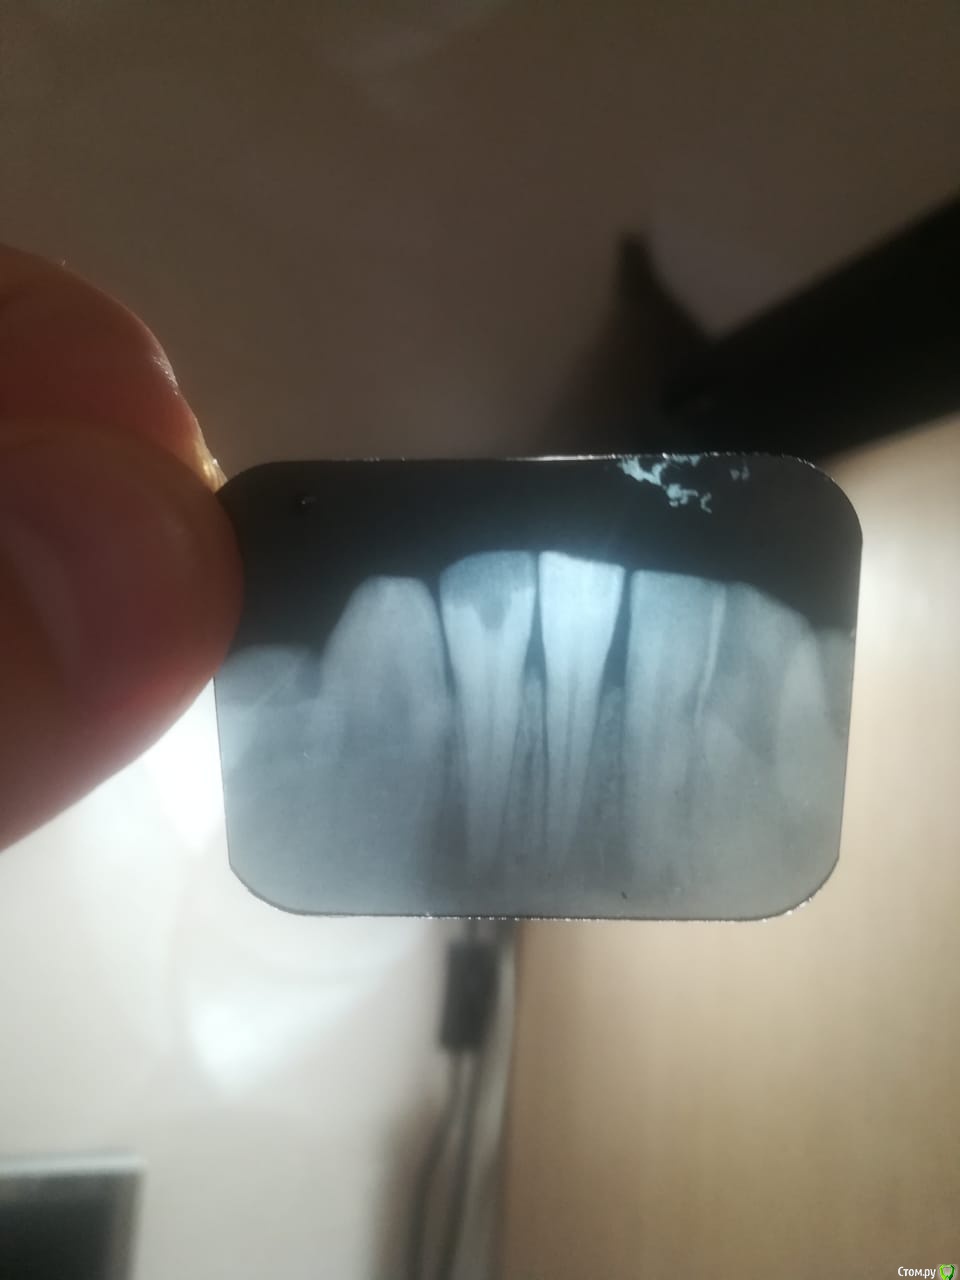

pa.moskovkin Опубликовано 9 сентября, 2019 Автор Поделиться Опубликовано 9 сентября, 2019 Во первых по правилам форума вы должны предоставить снимки для клинического анализа, во вторых с открытым зубом нельзя ходить, необходимо провести обработку канала зуба, опять же без снимка ничего не понятно. Обратитесь в хорошую стоматологию, где вам помогут используя современные протоколы. Добрый день!Снимок сделан непосредственно перед разрезом десны. Ссылка на комментарий

krokomot Опубликовано 9 сентября, 2019 Поделиться Опубликовано 9 сентября, 2019 Снимок малоинформативен, но хотя бы понятно, что зуб нормальный, как я и говорил необходимо снова провести качественную обработку и расширение канала, так как причина воспаления в микробах живущих внутри канала. Ссылка на комментарий